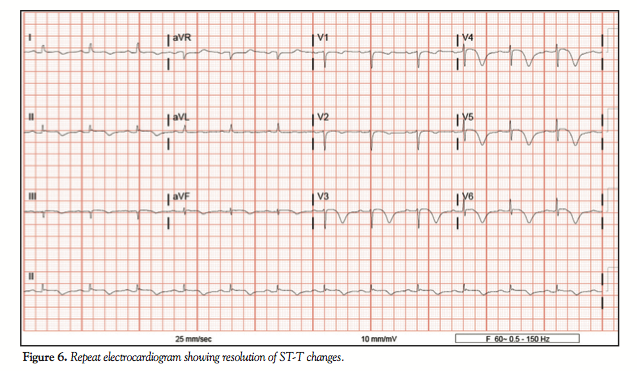

Case Report. An 80-year-old Caucasian woman with a history of hypertension and anxiety was admitted to the emergency department after initial presentation to her primary care physician with chest pain. Electrocardiogram (ECG) showed 1 mm ST-segment elevations in leads II, III, aVF, V3, V4, and V5 (Figure 1). A two-dimensional echocardiogram showed dyskinetic left ventricular apex and akinetic periapical segments along with hyperdynamic basal segments with an ejection fraction of 48% (Figure 2). The cardiac enzymes were mildly elevated, with a peak troponin I of 4.93 ng/mL. The patient was initially treated with beta-blockers, heparin, clopidogrel, atorvastatin, and aspirin, and was taken immediately for cardiac catheterization. Angiography revealed 50% proximal heavily calcified lesion of the left anterior descending (LAD) coronary artery and an 80% occ

lusive lesion at the trifurcation of the septal perforator and the diagonal branch of the LAD (Figure 3). The right coronary artery was a dominant vessel, with a proximal 50% focal calcified lesion. Left ventriculogram showed hyperdynamic basal, inferior, and anterior segments with dyskinetic anterolateral, apical, and inferior walls (Figure 4). Subsequently, the patient was placed on conservative medical therapy with uneventful hospital stay and then discharged. Repeat echocardiogram and ECG performed 3 weeks later showed resolution of wall-motion abnormalities and normalization of ejection fraction, along with resolution of ST-T changes, respectively (Figures 5 and 6).